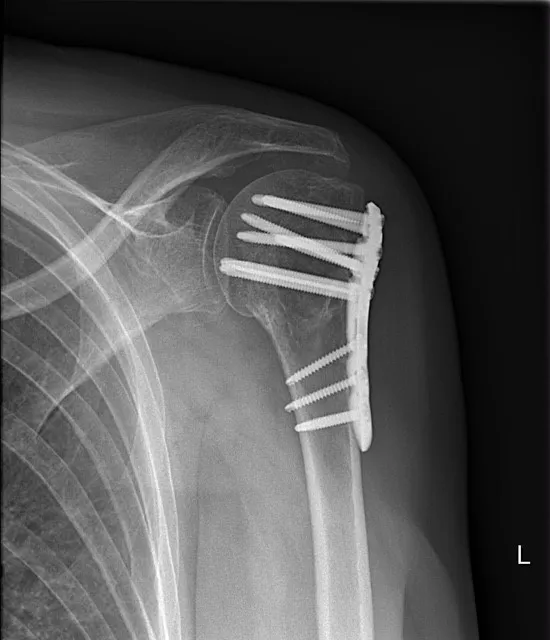

Stap 3: Operatie (bij instabiele breuk). Is de breuk ernstig verplaatst (zoals bij een verbrijzelde kop) of zijn er meerdere botfragmenten, dan is een operatie vaak de beste optie. Een schouderbreuk operatie is nodig om de botstukken weer in de juiste stand vast te zetten. De orthopedisch chirurg kan de breuk fixeren met metalen platen en schroeven of met een nagel in het bot. Deze ingreep gebeurt onder algemene verdoving. Na de operatie draagt u enkele weken een draagverband en start u al snel met fysiotherapie om verstijving te voorkomen. Bij zeer complexe breuken (bijvoorbeeld verbrijzelde kop bij een oudere patiënt) kiest men soms voor een kunstgewricht: de gebroken kop wordt vervangen door een omgekeerde schouderprothese.